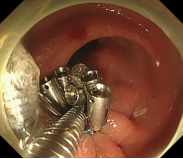

食管胃底静脉曲张内镜下套扎、组织胶治疗

肝硬化食管和胃底静脉曲张破裂出血的内镜下组织胶注射和套扎序惯治疗